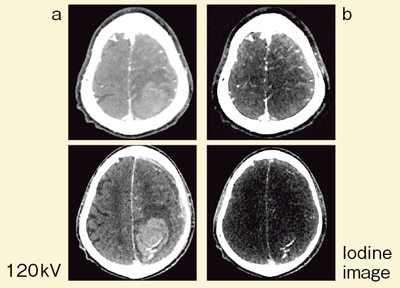

DEイメージングでは,100kVの画像と140kVの画像を撮影し,通常は,これらを加算平均した120kV相当の画像で診断を行うが,brain hemorrhageで処理すると,virtual noncontrast(疑似単純画像)とiodine image(ヨード画像)の2種類の画像を得ることができる(図5)。

● 症例1:早期相での造影効果

図6は頭部外傷で,単純CTにより,脳挫傷による血腫と硬膜下血腫が認められた症例である。造影CT(120kV相当の合成画像)では血腫内の造影効果の判定は難しいが(図6b),brain hemorrhageによるヨード画像では,淡い造影効果が認められる(図6d↑)。遅延相でも同じ部位での造影が認められたことから,早期相でも造影剤が描出されることがわかる症例である。

図6 症例1:早期相での造影効果